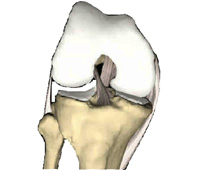

Le genou est l’une des articulations les plus grosses et les plus complexes du corps. Il se compose de l’extrémité inférieure du fémur qui effectue une rotation sur l’extrémité supérieure du tibia et de la rotule qui glisse dans une gouttière sur la partie fémorale. Des ligaments épais fixés au fémur et au tibia assurent la stabilité du genou. Les longs muscles de la cuisse renforcent l’articulation. L’arthroplastie totale du genou consiste à remplacer les parties blessées ou endommagées du genou par des implants artificiels. Votre nouveau genou sera formé d’un composant métallique fixé sur la partie fémorale, d’un insert en métal et en polyéthylène sur la partie tibiale et, si nécessaire, d’un insert rotulien en polyéthylène. Si vous avez des questions, adressez-vous à votre médecin ou votre chirurgien orthopédique.